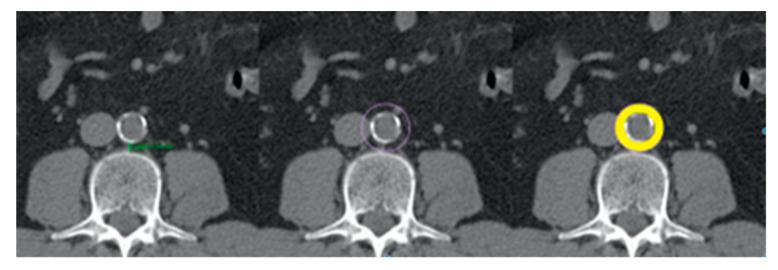

The prevalence of obesity has doubled, with a concomitant increase in cardiovascular disease. This study aimed to compare the characteristics of visceral, subcutaneous and peri-aortic adipose tissue determined with computed tomography (CT) scans and to correlate them with cardiovascular risk factors, anthropometric measures and medication. An observational and prospective study was conducted, and 177 subjects were included. Peri-aortic adipose tissue had the highest density, while the subcutaneous adipose tissue had the lowest. The density of subcutaneous adipose tissue differs from the density of visceral ( = 0.00) and peri-aortic adipose tissue ( = 0.00). Smokers/ex-smokers had a lower area ( = 0.00) and density ( = 0.02) of subcutaneous adipose tissue. Multiple linear regression analysis showed that sex was a predictor of subcutaneous adipose tissue area (β = -0.27, t = -3.12, = 0.00) but smoking habits were not. After controlling for sex, we found that the association between smokers/ex-smokers and area of subcutaneous adipose tissue was lost, but the association with density persisted. Patients with hypertension had a higher visceral adipose tissue area, and this relationship was maintained even after adjusting for gender. Peri-aortic adipose tissue is similar to visceral and distinct from subcutaneous adipose tissue. Cardiovascular risk factors have different influences in distinct adipose compartments.

摘要

肥胖的患病率已翻倍,同时心血管疾病也有所增加。本研究旨在比较通过计算机断层扫描(CT)确定的内脏、皮下和主动脉周围脂肪组织的特征,并将它们与心血管危险因素、人体测量指标和药物治疗相关联。进行了一项观察性前瞻性研究,纳入了177名受试者。主动脉周围脂肪组织密度最高,而皮下脂肪组织密度最低。皮下脂肪组织的密度与内脏脂肪组织(P = 0.00)和主动脉周围脂肪组织(P = 0.00)的密度不同。吸烟者/戒烟者的皮下脂肪组织面积较小(P = 0.00)且密度较低(P = 0.02)。多元线性回归分析表明,性别是皮下脂肪组织面积的预测因素(β = -0.27,t = -3.12,P = 0.00),但吸烟习惯不是。在控制性别后,我们发现吸烟者/戒烟者与皮下脂肪组织面积之间的关联消失,但与密度的关联仍然存在。高血压患者的内脏脂肪组织面积较大,即使在调整性别后这种关系依然存在。主动脉周围脂肪组织与内脏脂肪组织相似,与皮下脂肪组织不同。心血管危险因素在不同的脂肪隔室中有不同的影响。